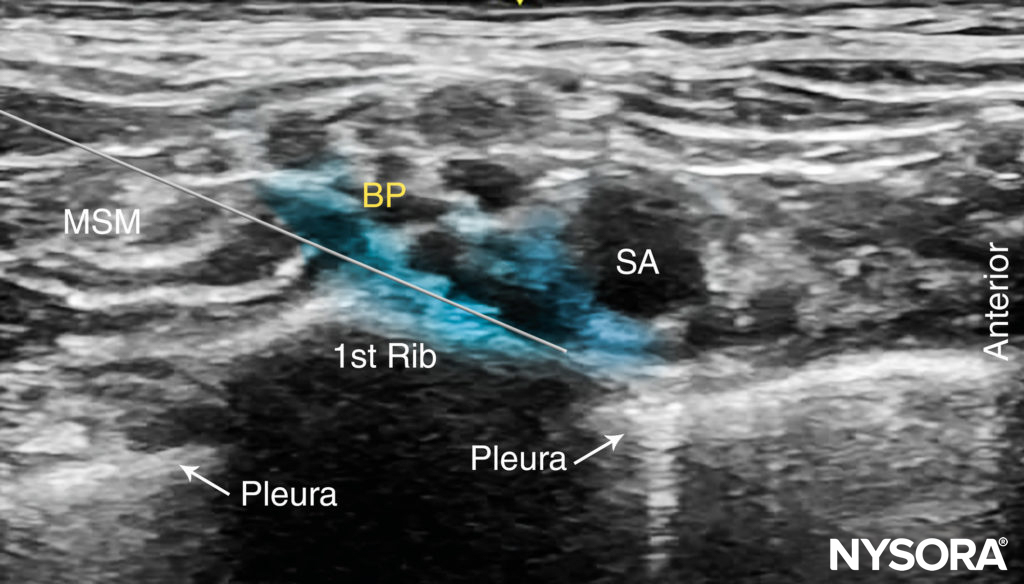

ULTRASOUND ANATOMY

The subclavian artery crosses over the first rib between the insertions of the anterior and middle scalene muscles, posterior to the midpoint of the clavicle. The subclavian artery is readily apparent as an anechoic round structure, whereas the parietal pleura and the first rib can be seen as a linear hyperechoic structure immediately lateral and deep to the subclavian artery (Figure 3). The rib casts an acoustic shadow so that the image field deep to the rib appears anechoic.2 The brachial plexus can be seen as a bundle of hypoechoic round nodules just posterior and superficial to the artery (Figures 3 and 4). It is often possible to see the fascial sheath of the muscles surrounding the brachial plexus. Adjusting the transducer orientation, the upper, middle and lower trunks of the brachial plexus can be individually identified, as they join together at the costoclavicular space. To visualize the lower trunk, the transducer is oriented in the sagittal plane, until the first rib is seen deep to the plexus and the artery. (Figure 4). Anterior or posterior to the first rib is the hyperechoic pleura, with lung tissue deep to it. This structure can be confirmed by observing a “sliding” motion of the viscera pleura in synchrony with the patient’s respiration. The brachial plexus is typically visualized at a 1- to 2-cm depth at this location. The presence of two separate clusters of elements of the brachial plexus may be more or less obvious, sometimes with separation by a blood vessel (Figure 4). The dorsal scapular artery commonly passes through or within the vicinity of the brachial plexus. It is important to recognize that the more superficial and lateral branches come from C5–C7 (shoulder, lateral aspect of arm, and forearm) and can be tracked up to the interscalene area, whereas the deeper and more medial contingent are branches of C8 and T1 (hand and medial aspect of forearm). Adequate spread of local anesthetic in both areas is necessary for successful nerve block of the arm and hand. For additional information see Functional Regional Anesthesia Anatomy.

FIGURE 3. Supraclavicular brachial plexus (BP; yellow arrows) seen slightly superficial and posterolateral to the subclavian artery (SA). The brachial plexus is enveloped by a connective tissue sheath. Note the intimate location of the pleura and lung to the brachial plexus and subclavian artery. MSM, middle scalene muscle.

With the patient in the proper position, the skin is disinfected and the transducer is positioned in the transverse plane immediately proximal to the clavicle, slightly posterior to at its midpoint. The transducer is tilted caudally, as if to image the chest contents, to obtain a cross-sectional view of the subclavian artery (Figure 5). The brachial plexus is seen as a collection of hypoechoic oval structures posterior and superficial to the artery. Color Doppler should be routinely used prior to needle insertion to rule out the passage of large vessels (ie, dorsal scapular artery, transverse cervical artery, suprascapular artery) in the anticipated trajectory of the needle.

Using a 25- to 27-gauge needle, 1–2 mL of local anesthetic is injected into the skin 1 cm lateral to the transducer to decrease discomfort during needle insertion. To avoid inadvertent puncture of and injection into the brachial plexus, the needle should not be initially inserted deeper than 1 cm. The distribution of local anesthetic via small-volume injections is observed as the needle advances through tissue layers (hydro-localization); small-volume injections are used to avoid inadvertent needle insertion into the brachial plexus. The nerve block needle is then inserted in plane toward the brachial plexus, in a lateral-to-medial direction (Figures 5 and 6).